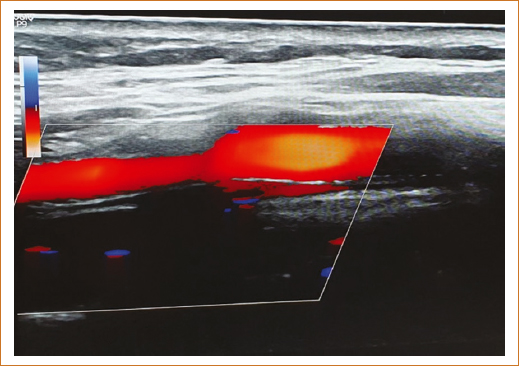

La paciente continuó con manejo médico con restricción hídrica, insulina de acción rápida por requerimientos, furosemida 10 mg/12 h, apixabán 2.5 mg/12 h, atorvastatina 40 mg/24 h y esomeprazol 40 mg/24 h por vía intravenosa. No presentó deterioro de la función renal y en las siguientes 72 horas la nueva depuración de creatinina se reportó en 42 ml/min. Metabólica y hemodinámicamente continuó compensada y neurológicamente consciente, orientada, Glasgow 15 puntos, sin déficit motor focal, movilizando sus cuatro extremidades con fuerza muscular normal, reflejos de estiramiento muscular normales acorde a su edad, no disártrica, no disfágica, sin ataxia, íntegra de juicio y raciocinio, marcha normal, tolerando la vía oral y sin compromiso en sitios de arteriopunción. La paciente egresó por mejoría 5 días después del cateterismo, con tratamiento multidisciplinario y seguimiento en la consulta externa de medicina interna. Desde entonces hasta septiembre de 2025 presenta mejoría de su clase funcional cardiaca, estabilidad metabólica con HbA1c < 7.4% y estabilidad hemodinámica con presión arterial promedio 146/84 mmHg. El ultrasonido Doppler carotídeo de control tardío del 11 de septiembre 2025 mostró stent carotídeo estable, con adecuado flujo sanguíneo (Figs. 3 y 4). Las radiografías simples de cuello permitieron identificar fácilmente el stent, su ubicación y la ligera estenosis residual (Fig. 5).

Figura 3. Ultrasonido Doppler carotídeo.

Figura 4. Ultrasonido Doppler color carotídeo.